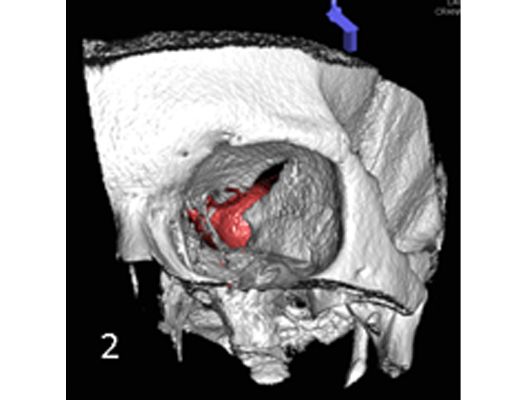

Angiographie: Behandlung von Aneurysmen

Behandlung von Aneurysmen

Aneurysmen an der Gefäßen des Gehirns können in vielen Fällen minimalinvasiv durch einen Zugang durch das Gefäßsystem, zumeist von der Leiste aus behandelt werden (sog. Endovaskuläre Therapie). Dabei gibt es z.B. die Möglichkeit ein Aneurysma durch Einbringung von Platinspiralen zu verschließen (sog. Coiling). Auch für komplexe Aneurysmen stehen inzwischen verschiedene endovaskuläre Methoden zur Verfügung.

Das Beispiel zeigt die angiographischen Bilder einer Patientin, bei der es zu einer Sehstörung gekommen war. Die Ursache war ein großes Aneurysma der Halsschlagader an der Schädelbasis (Bild 1). Bild 2 zeigt die Lage des Aneurysmas hinter dem Auge. Durch den Druck des Aneurysmas auf den Sehnerv war es zu der Sehstörung gekommen. Die Patientin wurde mit einer speziellen Gefäßprothese versorgt, welche über eine Punktion der Leistenarterie in die Halsschlagader eingesetzt wurde (Bild 3). Bei der Kontrolle nach 6 Monaten zeigte sich ein vollständiger Verschluss des Aneurysmas (Bild 4). Die Sehstörung hatte sich vollständig zurückgebildet.